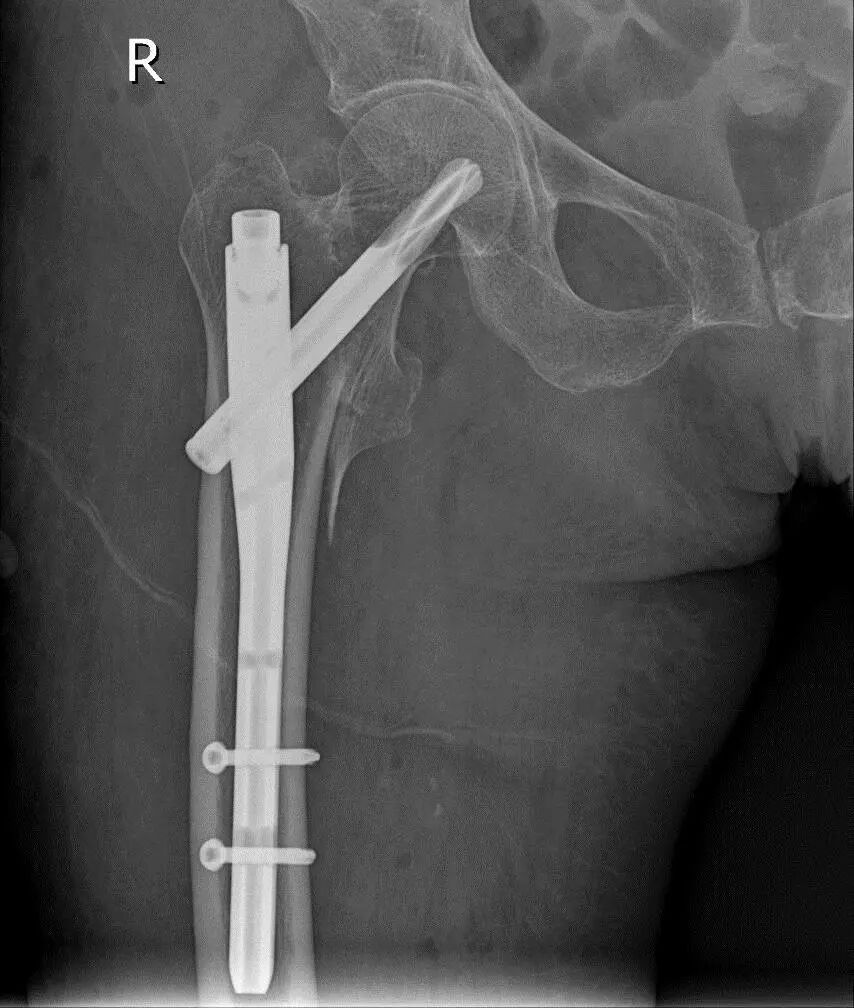

术后X线片

手术当天8:30,首先由心内一科张文媛医师在手术室复合手术间为患者行心脏介入手术植入心脏临时起搏器。为配合骨科髋部手术,穿刺点选取颈部。9:00,心脏临时起搏器植入成功,心率设定在70次/ 分。随即,麻醉医师王敬给与患者全身麻醉,并密切监测生命体征。9:40,骨一科张军主任团队行股骨粗隆间骨折的闭合复位,并置入PFNA内固定髓内钉。11:20,手术顺利完成,患者生命体征平稳。术后第二天,患者疼痛明显缓解,已能在床上坐起进食。